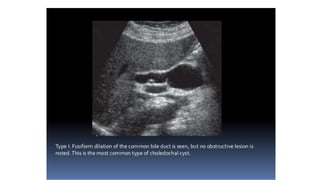

USG

• Ballooned/fusiform cyst beneath porta hepatis separate from GB

• *Communication with bile duct needs to be demonstrated*

• Abrupt change of caliber at junction of dilated segment to normal

ducts

• Intrahepatic bile duct dilatation secondary to stenosis.

USG • Ballooned/fusiform cystbeneath porta hepatis separate from GB • *Communication with bile duct needs to be demonstrated* • Abrupt change of caliber at junction of dilated segment to normal ducts • Intrahepatic bile duct dilatation secondary to stenosis.